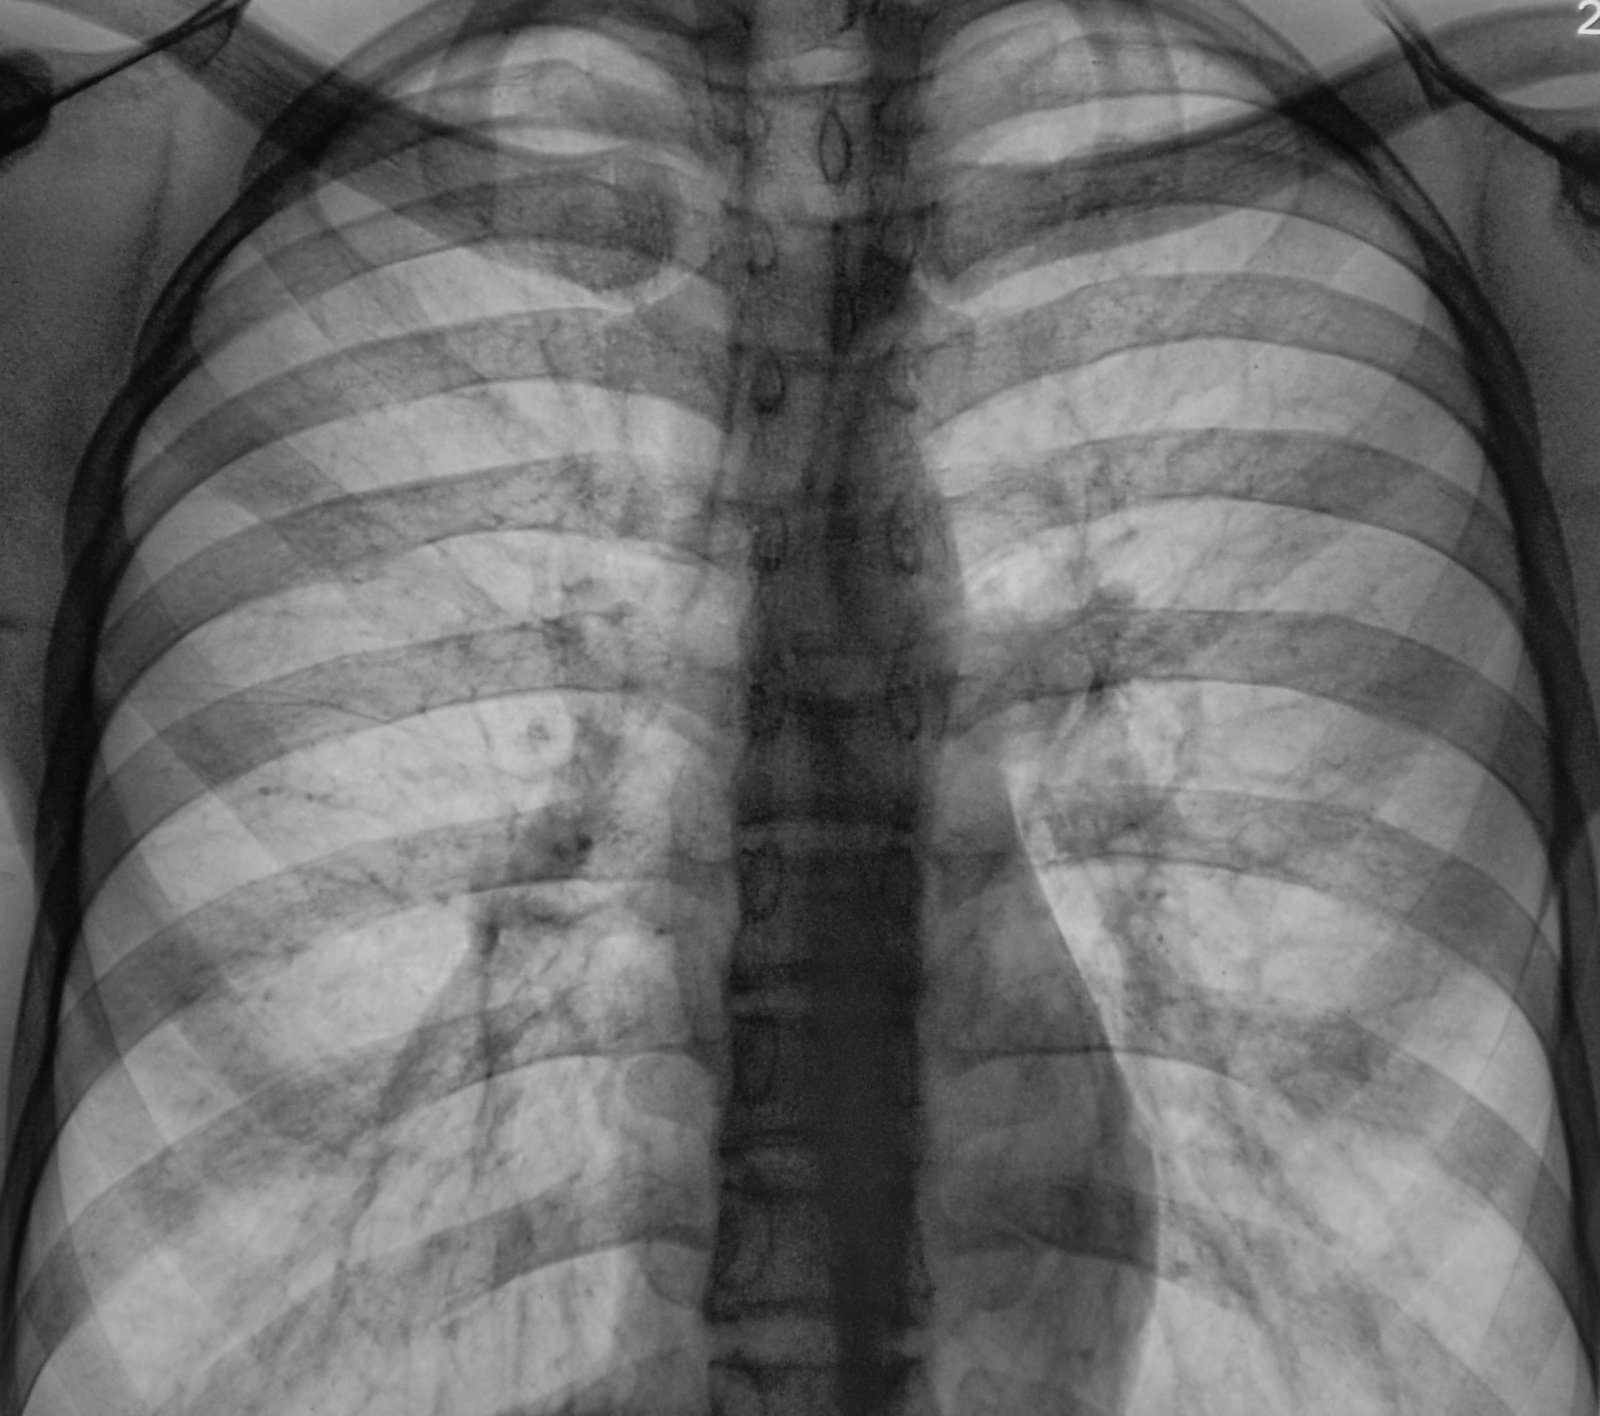

Туберкульоз вже давно перестав бути «хворобою жебраків» і з 1995 року кошмарить Україну (куди там заморському коронавірусу! Тисячі померлих щороку – і ніякої паніки). Його збудник – паличка Коха – надзвичайно стійка у зовнішньому середовищі. В нашій країні офіційно оголошена епідемія. Незважаючи на це, заповзятлива колишня і. о. Міністра охорони здоров’я Уляна Супрун прийняла рішення згорнути існуючу на той момент систему ранньої діагностики і лікування. Сюрреалізм: інфекцію, названу Всесвітньою організацією охорони здоров’я найбільш смертоносною, пропонують лікувати на дому (!!!), а щорічну флюорографію замінити опитуванням у дільничного лікаря. Тобто до нього спершу потрібно дійти, а потім відповісти на ряд питань. Але це не обов’язково. І ми, звичайно, всі за гуманізм, але уявляти, що саме вашого сусіда по під’їзду лікують таким чином від смертельного і дуже заразного захворювання, якось не хочеться, вірно? Ліфт і вентиляцію йому окремі не нададуть.

І, поки батьки дітей, що вже заразилися в школі, і поки ще здорових учнів, бігають по інстанціях, в Запоріжжі просто закривають три з чотирьох тубдиспансерів. А співробітників єдиного, що залишився, скорочують і переводять на мінімальну оплату праці, позбавивши всіх виплат за шкідливість. Чи захочуть люди працювати з мікробом-вбивцею за мізерні гроші, або підуть в приватні лабораторії – риторичне питання. Як і те, що буде з кожним читачем цієї статті. Паличка Коха прекрасно почуває себе в пилюці там, де ви ведете дитину в садок. І в будь-якому супермаркеті. І навіть в класі, де вчаться ваші діти. Але ні медиків, готових боротися з нею, ні їх робочих місць, не залишилося в Запоріжжі, яке впевнено входить до п’ятірки найбільш неблагополучних з туберкульозу міст України. І по дитячому, і по дорослому.